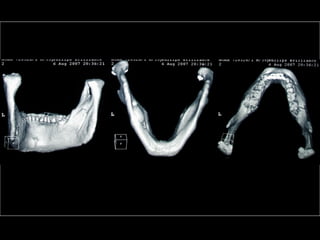

Diagnóstico en Implantología

• Clínico

• Por Imágenes Rx. Tomografía

Diagnóstico por Imágenes

• Rx Extraorales: Teleradiografías y

Ortopantomografías

• Rx intraorales: Oclusales y Rx. Periapicales.

• Fundamentalmente Tomografías

Tomografía Convencional

(sobre película)

Poseen distorsiones homogéneas, estandarizadas

y calculadas para cada tipo de aparato

Tomografía Computada